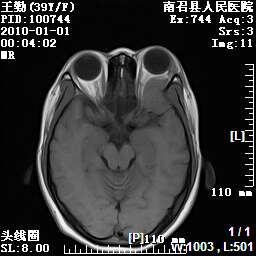

以下是引用随光逐影在2010-1-22 9:03:00的发言:[br]考虑左侧中颅窝(蝶骨翼区)脑膜瘤侵犯蝶骨翼并突入左侧眼眶。

以下是引用水过无痕在2010-1-22 14:55:00的发言:[br]一、定位:颅外占位;二、定性:恶性可能性大;三、组织来源:来源于左侧眼外直肌或其他部位;考虑为:横纹肌肉瘤>转移瘤>脑膜瘤.